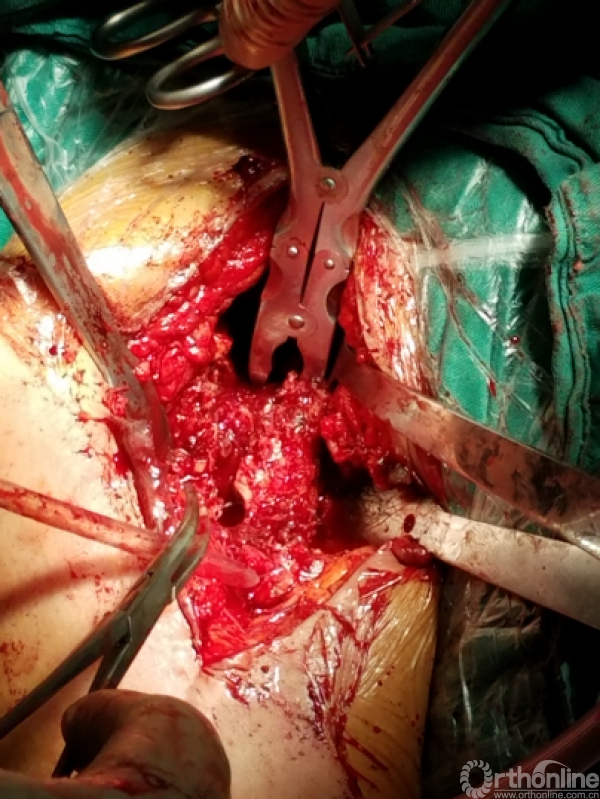

显露出肱骨头假体柄处

开始向内上扩大显露

注意事项: 肱骨头内移至喙突处,位于后内侧下方已有骨桥连接

特别小心腋鞘及臂丛神经

提示无法顺利脱位!!!

小心咬出间隙后,牵引肘关节前屈肩关节后伸外旋,拉钩撬拨脱位!!

关节盂正常结构消失,至喙突偏内侧部位,上方紧贴肩峰下,仍然有骨质可用!

咬除连接骨桥,清理髓腔,恢复活动度